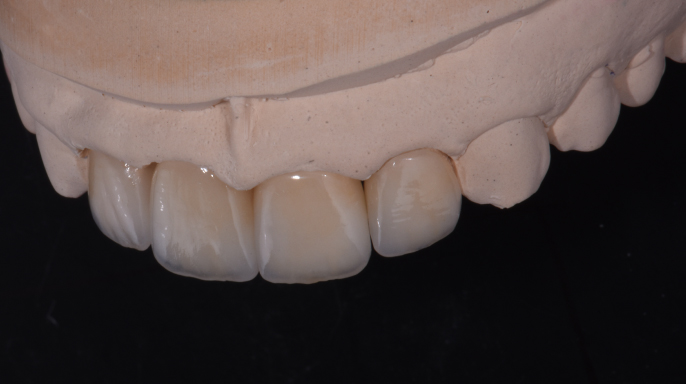

EndodonciePacient se dostavil do ordinace, nespokojený s estetickým výsledkem korunek na zubech 24 a 25. Klinické vyšetření prokázalo nevyhovující marginální uzávěr u obou korunek, a proto bylo indikováno zhotovení nových protetických rekonstrukcí.

PR, Zirkonzahn | Případ Dr. Anne-Maree Cole – The Littleton Cole Dental Centre, Brisbane, Austrálie, a DT Werner Sauer – Werner Sauer Smile Design, Brisbane, Austrálie

Klinický přístup k plně keramickým hybridním rehabilitacím zajišťujícím dlouhodobou stabilitu a vysoce estetické výsledky bez použití kovových komponent.

Multidisciplinární případ ukazující univerzálnost materiálu IPS e.max Ceram pro dosažení přirozeného a vysoce estetického výsledku.